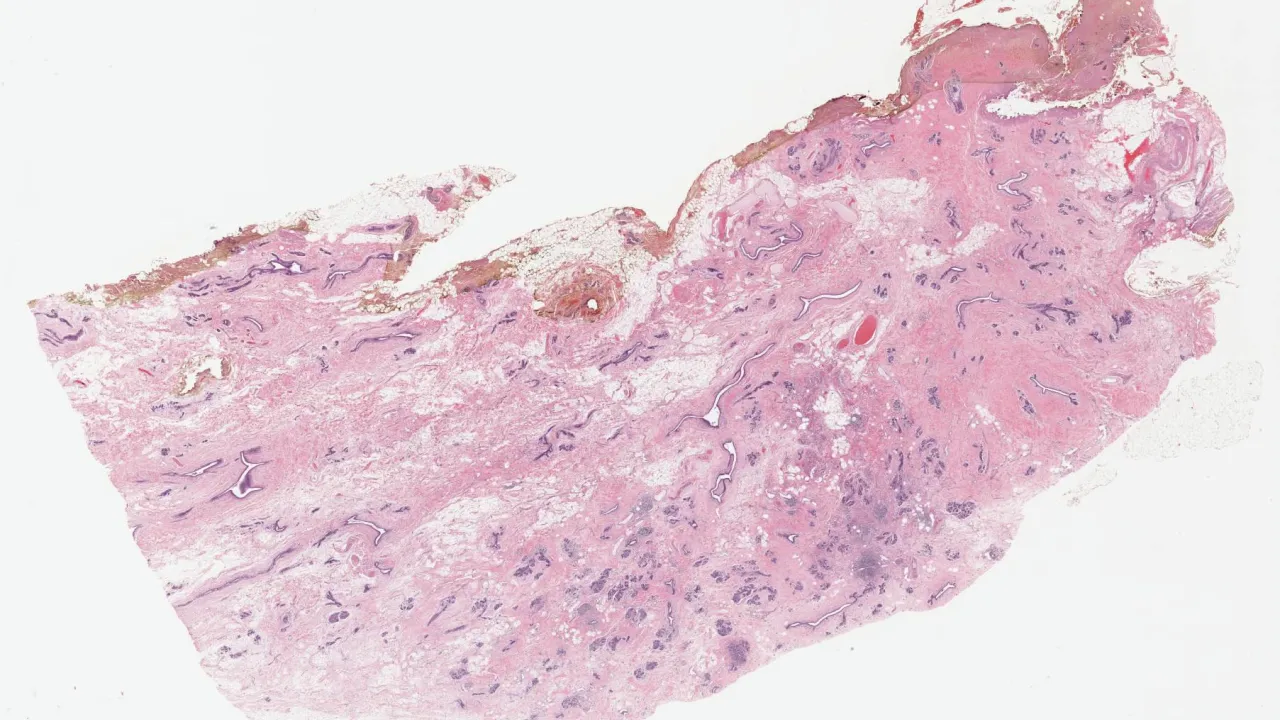

Breast, Epithelial-myoepithelial invasive carcinoma, p63 stain